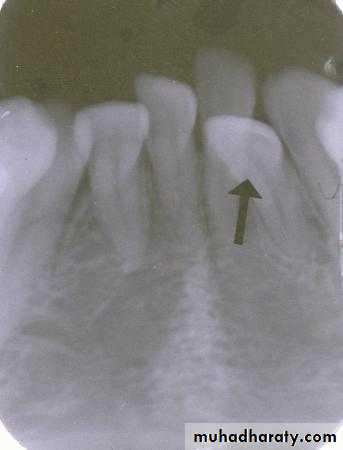

incisor film

canine filmIs the displaced incisor (arrows) located on the buccal or the lingual?

The lateral incisor is displaced to the lingual. The tube head moves distally from the incisor film to the canine film. The lateral incisor also moves distally, covering half the canine on the canine film.